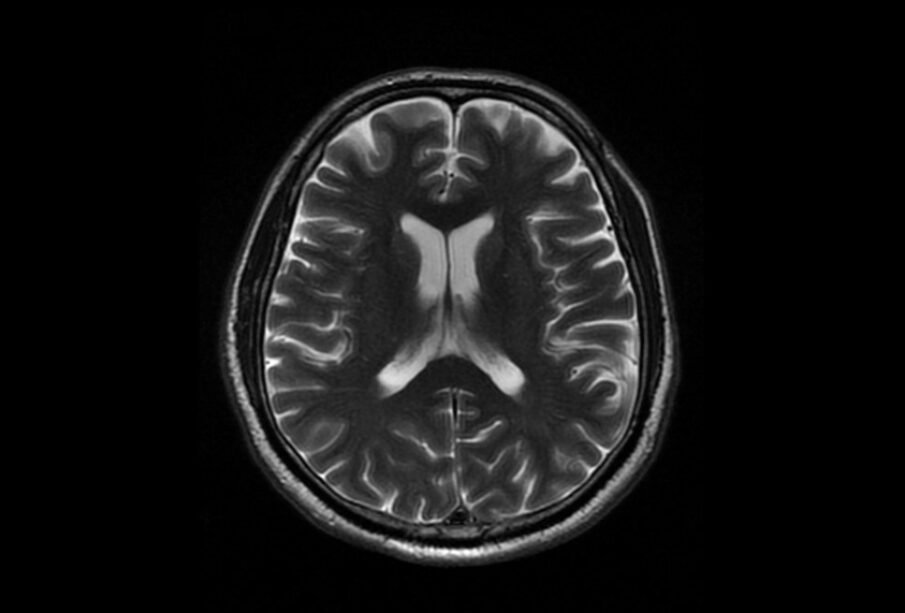

Attēldiagnostikas izmeklējumi

Audzēja klātbūtni un tā raksturojumu visbiežāk nosaka ar radioloģiskām metodēm. Ikdienas praksē visbiežāk izmanto galvas smadzeņu magnētiskās rezonanses izmeklējumu vai datortomogrāfiju. Šie izmeklējumi ļauj novērtēt audzēja izmēru, precīzu lokalizāciju un palīdz diferencēt dažādus veidojumu tipus.

Lai uzlabotu precizitāti, nereti tiek ievadīta kontrastviela, kas palīdz labāk izcelt audzēju un tā robežas. Atsevišķās situācijās, piemēram, operācijas plānošanā vai sarežģītos gadījumos, var izmantot specializētas metodes, tostarp funkcionālo magnētisko rezonansi vai pozitronu emisijas tomogrāfiju.

Dažādiem audzēju veidiem attēldiagnostikā mēdz būt raksturīgas pazīmes. Daļa audzēju, piemēram, oligodendrogliomas, var radīt kalcija nogulsnes, kas datortomogrāfijā parasti ir labi saskatāmas. Glioblastomas bieži aptver vairākas galvas smadzeņu zonas, savukārt metastāzes nereti veidojas sīko asinsvadu tuvumā.